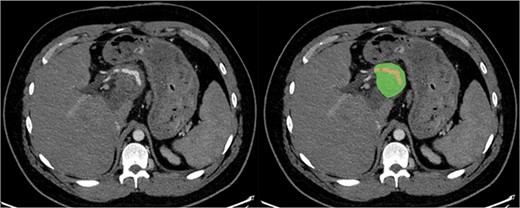

Due to the debilitating nature of the patient’s condition and his wishes for an attempt at treatment, he was brought forward for a further exploratory laparotomy. The patient’s rooftop incision was reopened and the wound and sinus tract were excised en bloc. The stomach and transverse colon were found to be densely adherent to the teratoma. These were carefully mobilized and dissected free from the teratoma. Again, resectability of the teratoma was assessed and deemed to be impossible due to the hepatic artery being inseparable from the lesion (Fig. 2). Instead, internal drainage with diversion of the sinus discharge via a jejunostomy with a Roux en Y reconstruction of the alimentary tract was performed. The jejunum was divided at 50 cm from the duodenojejunal (DJ) flexure and the Roux limb was brought up to the origin of the sinus through a window made in the mesentery of the transverse colon. The lumen was opened and sutured over the origin of the sinus with 4/0 PDS sutures (Fig. 3). Finally, a jejunojejunostomy was formed to return continuity to the jejunum.

Sagittal section of post-operative CT with portal venous contrast demonstrating cystojejunustomy, highlighted in green, anastomosed to the origin of the fistula.